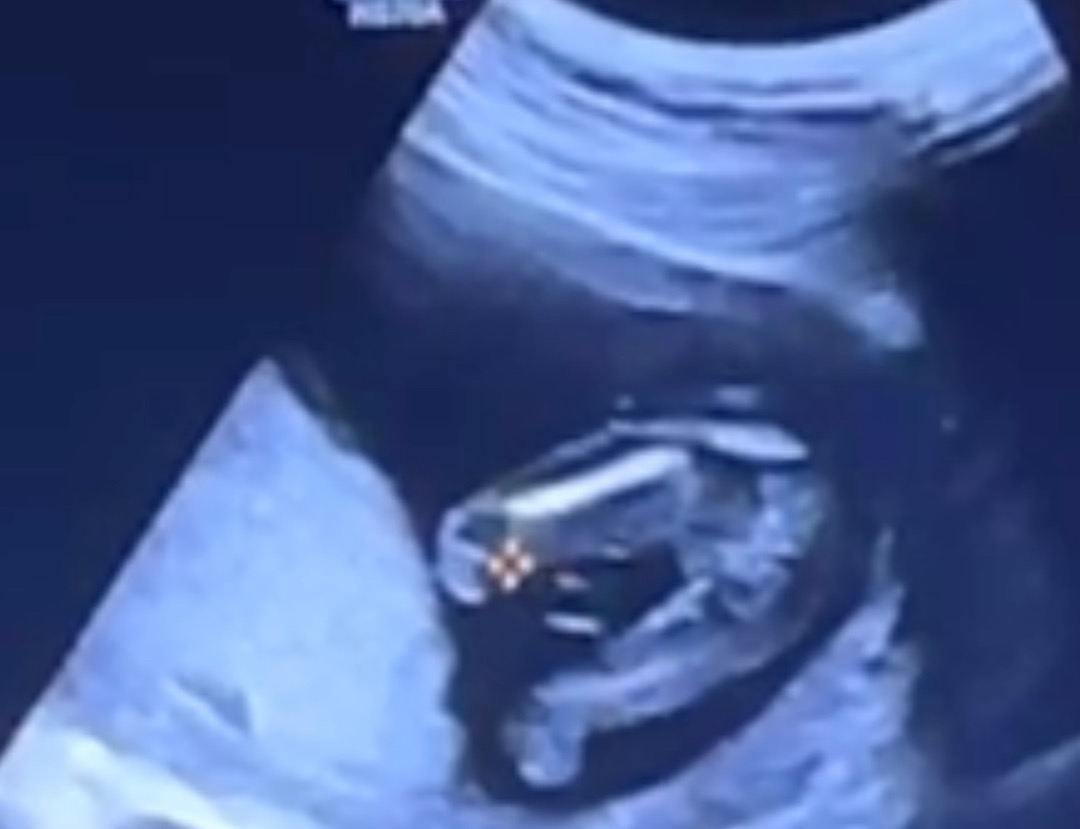

질문할게 너무 많아서 제일 궁금했던 성별을 못 물어보고 왔어요. 초음파보면서 딸인거 같다는 생각이 들었어서 그런지 질문하는걸 잊었네요 ㅎㅎㅎ 사진상으로도 확실하죠? ㅎㅎ